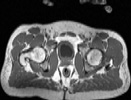

Visible Human male: Sectio transversalis 1886

CT

NMR

Pd                          / T2 \                         T1